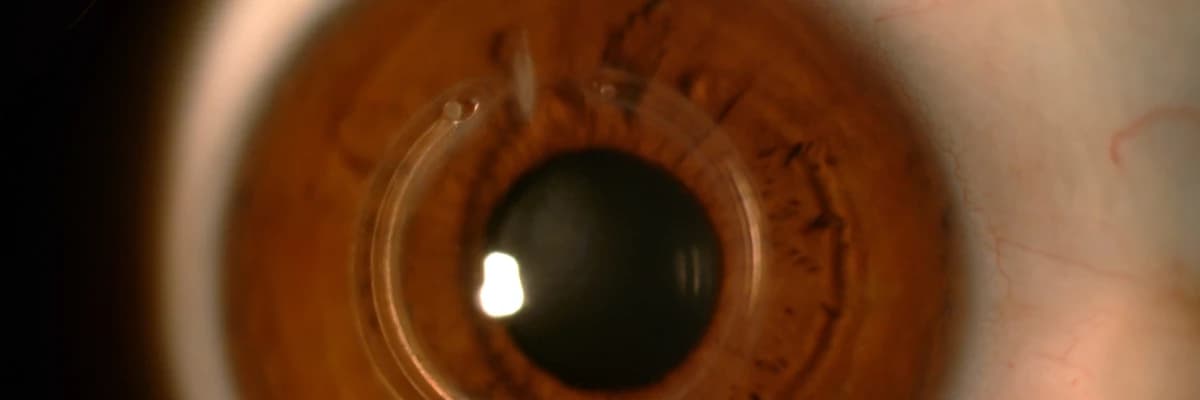

Keratokonus gözün ön bölümündeki saydam tabaka yani kornea tabakasının düzgün kubbemsi şeklinin bozulması, giderek incelmesi ve sivrilmesi ile karakterize bir kornea hastalığıdır.

Keratokonus çok ilerlediğinde gözün ön bölümünde korneanın konik biçimde

sivrildiği fark edilir, korneada nedbeler oluşabilir. Hastanın bu evrede görme

keskinliği çok düşüktür. Gözlük ve kontakt lens kullanamaz.